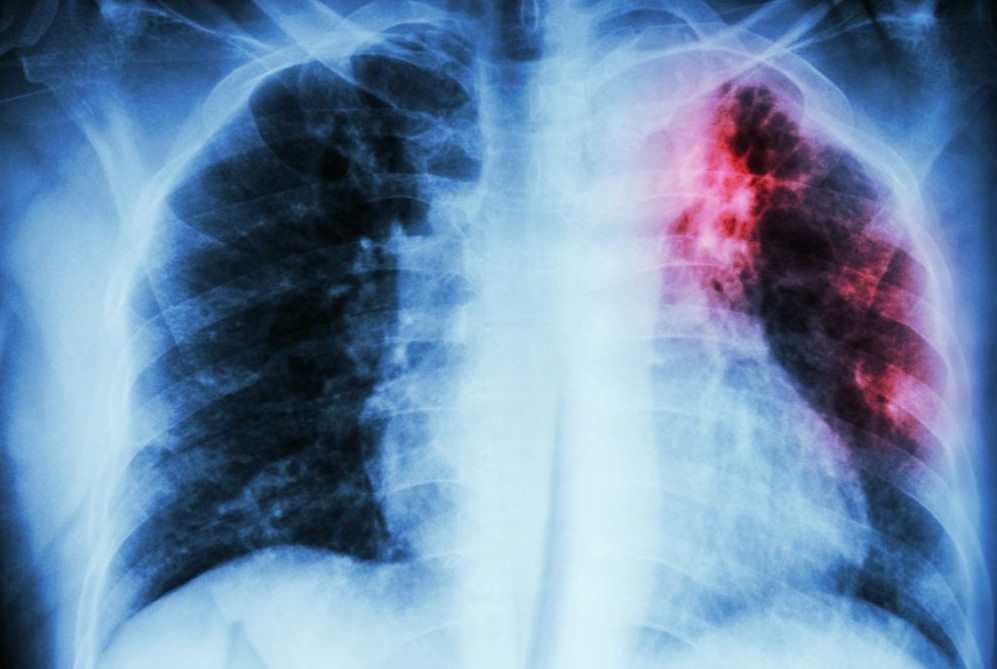

Di tengah perjuangan global melawan penyakit menular, diagnosis yang lambat seringkali menjadi penghalang utama. Bayangkan, sebuah penyakit kuno seperti tuberkulosis (TBC) masih menjadi momok mematikan, salah satunya karena metode deteksi konvensional yang memakan waktu. Namun, kini hadir sebuah terobosan signifikan: Tes Cepat Molekuler (TCM), sebuah revolusi yang mengubah peta pertarungan melawan TBC dengan kecepatan dan […]